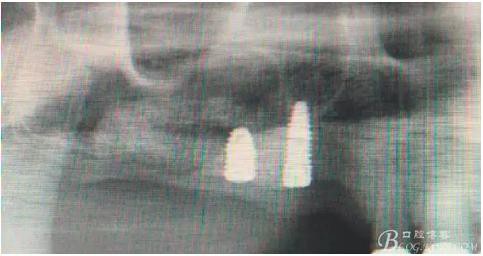

術后40天X光片。